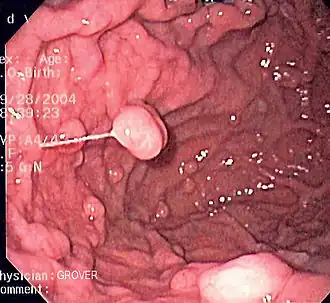

Эндоскопические исследования выполняются с помощью специальных аппаратов-эндоскопов, вводимых пациенту через естественные отверстия — рот или задний проход и передающих изображение в исследуемом органе или на окуляр эндоскопа или на монитор. В современной практике используются два типа гибких эндоскопов: волоконно-оптические фиброэндоскопы и видеоэндоскопы, оцифровывающие видимую в объектив картинку и передающие её в таком виде на монитор или окуляр. Эзофаго-, гастро-, дуодено- и/или еюноскопия показаны при подозрении на воспаление или язву, а также другие заболевания пищевода, желудка, тонкой кишки, фатерова сосочка. Колоноскопия — эндоскопическое исследование толстой кишки, показана при наличии клинических признаков, указывающих на поражение толстой кишки, наблюдении за пациентом в процессе лечения, при осмотрах, направленных на выявление на ранней стадии онкологических и других заболеваний[22].

Полипы фундальных желёз желудка. Изображение получено с помощью фиброгастроскопа